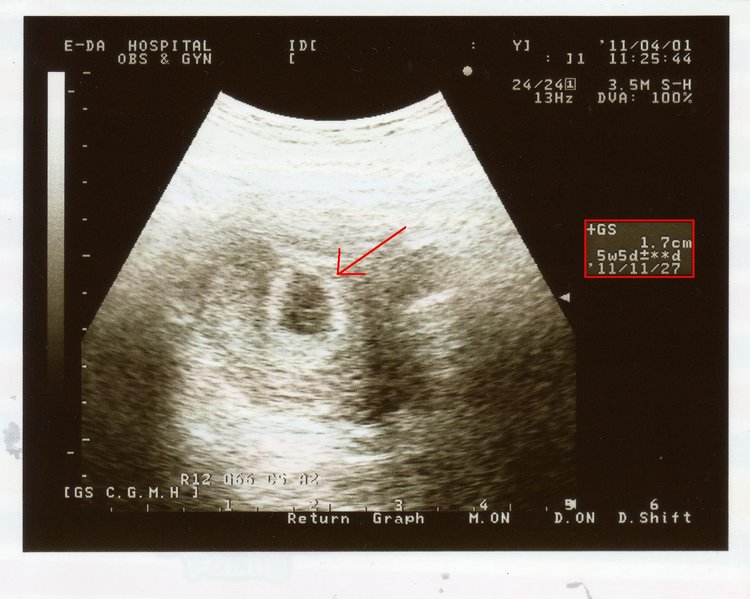

而且超音波照片上~寫著1.7cm約5W5D

跟我照月經算的週數明顯差了一週

我今天有問醫生~寶寶這樣有長大嗎?

他跟我說~上次(3月16日)還沒照到胚胎

這次有照到~所以是有長大~要我不要擔心!

可是後來回家我才發現週數似乎不太對